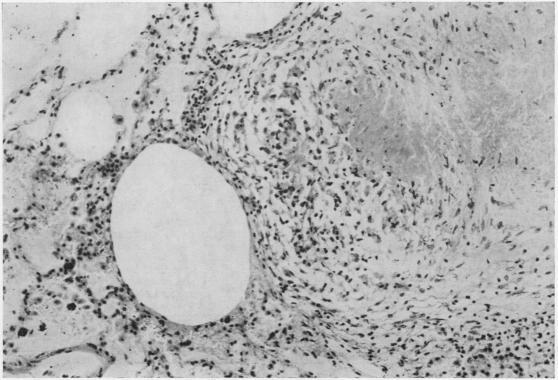

Non-reactive tuberculosis.

J Clin Pathol. 1954 Aug;7(3):216-25. doi: 10.1136/jcp.7.3.216.